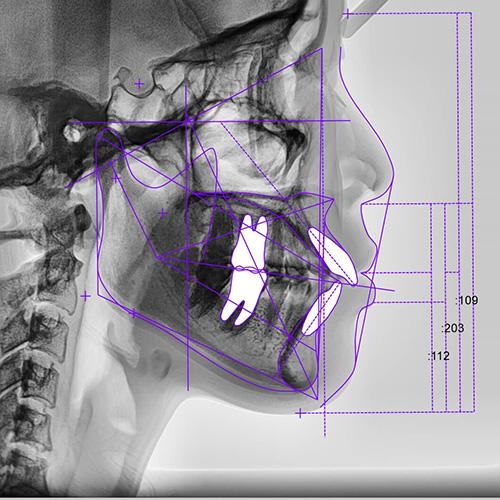

当院では、一定の規格に基づいて頭部や顔を正面・側面から撮影できる「セファログラム」(頭部X線規格写真撮影装置)を導入しています。顎の大きさ・形やズレ、歯の傾斜、口元のバランスなどを把握できる装置で、経時的に撮影することで、骨格の成長の変化や歯の移動を観察できます。

このセファログラムを使うことで、根拠に基づき客観的に分析できます。

矯正治療において、正確性に優れた診断・治療を行なうために不可欠な装置です。